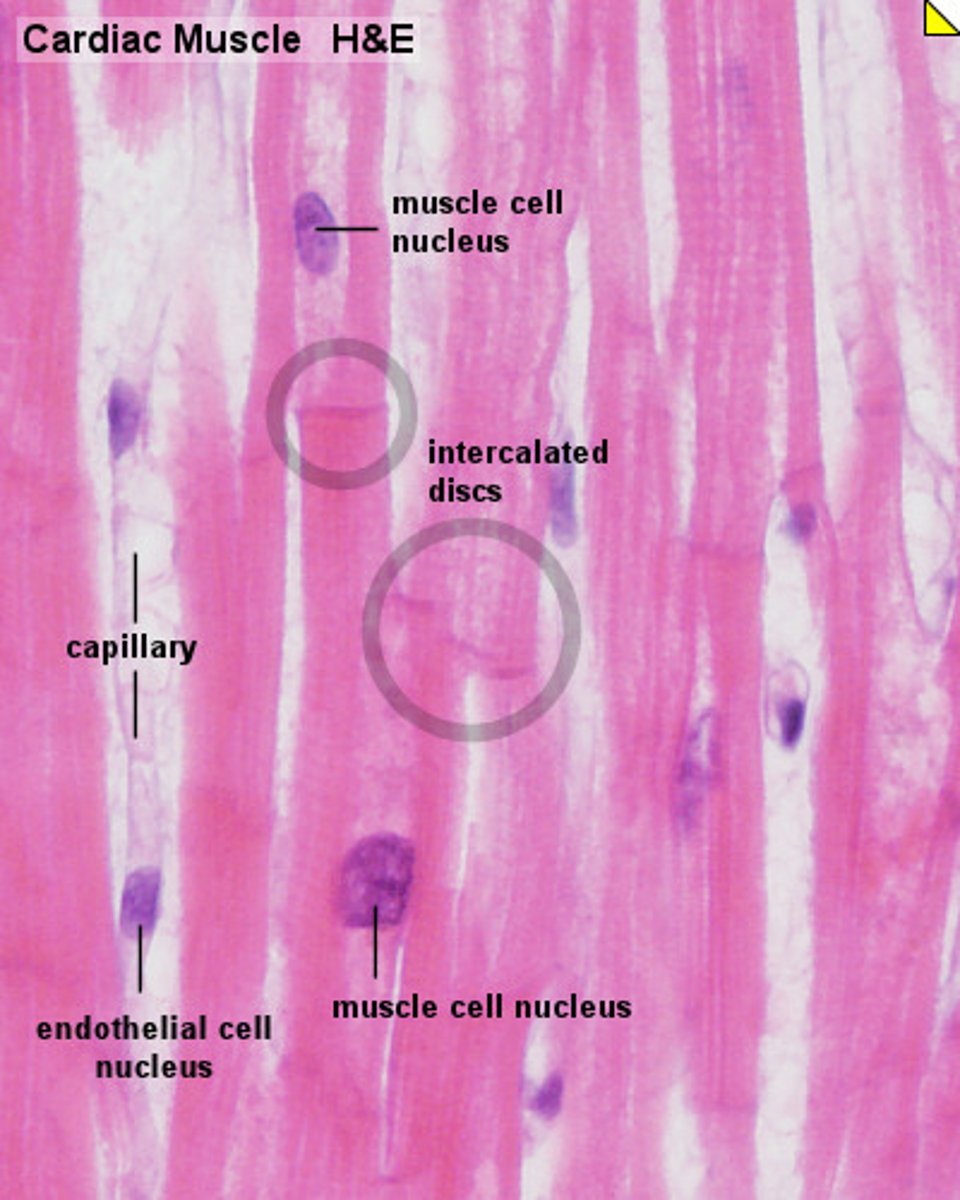

What are the 3 types of muscle tissue?

skeletal, cardiac, smooth

What is the structure, function, and location of cardiac muscle tissue?

Found in the walls of the heart, cells attached by intercalated disc, only muscle type***

How does cardiac tissue look

intercalated discs* only muscle type*, involuntary controlled, striations